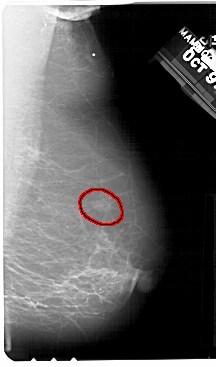

A_1357_1.RIGHT_MLO

LEFT_MLO LINES 5491 PIXELS_PER_LINE 3226 BITS_PER_PIXEL 12 RESOLUTION 43.5 NON_OVERLAY

FILE: A_1357_1.RIGHT_MLO.OVERLAY

TOTAL_ABNORMALITIES 1

ABNORMALITY 1

LESION_TYPE MASS SHAPE OVAL MARGINS ILL_DEFINED

ASSESSMENT 4

SUBTLETY 3

PATHOLOGY BENIGN

TOTAL_OUTLINES 1

BOUNDARY